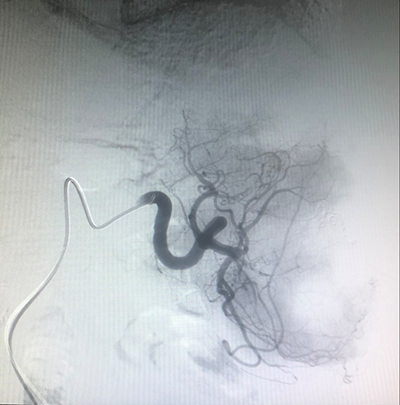

(介入術(shù)中操作)(肝癌的介入治療)

(肺癌的介入治療)(盆腔惡性腫瘤的介入治療)

(腦腫瘤的介入治療)(子宮肌瘤的介入治療)